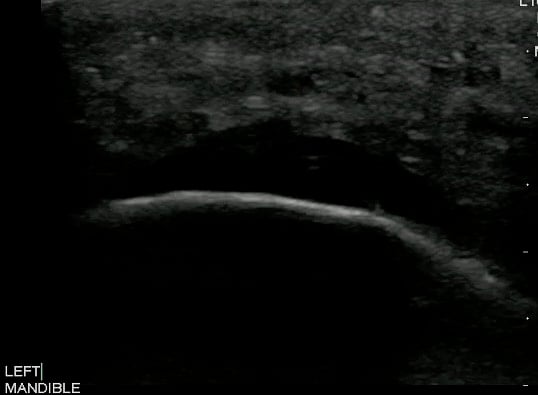

- Figure 5 and 6. Normal Mandible

- Bony structures like mandible, maxilla appear hyperechoic with a posterior hypoechoic acoustic shadow underneath.

- Fat has hyperechoic appearance on ultrasound.

- Muscles are generally visualized as hypoechoic structures but have a more heterogeneous striated appearance.

- Normal Mandible:

Video 4. Normal Mandible